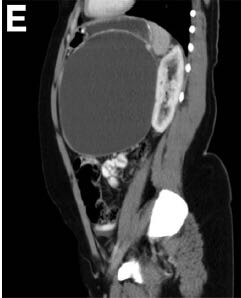

3个月前,她被电击中摔伤了腹部。当时这引起了上腹部疼痛;然而,她没有立即去医院直到3个月后才就诊。 该患者之前没有明显的病史或手术史,是一个非吸烟者,偶尔饮酒。 身体检查发现该女性健康,营养状况良好,唯一值得注意的是,腹部浅触诊时可于上腹部触及一个明显的肿块。 血常规检查包括全血细胞计数,尿素氮,电解质,葡萄糖,以及肝功能检查,均在正常范围内。血清淀粉酶66U/L,白蛋白43g/L,HIV 1/2 Ab/Ag酶联免疫吸附试验为阴性。 腹部对比增强计算机断层扫描显示连续轴向截面如图A-D。图E为矢状面。 剖腹手术时吸出低黏度,清澈,囊液,囊液生化分析显示,淀粉酶58903U/L,乳糖脱氢酶904U/L,蛋白质<10g/L。未获取囊性癌胚抗原和CA-19-9。在剖腹手术时对多个囊壁活检取样(图F)。

计算机断层扫描证实源自胰尾的一个大型,单房,囊性肿块,伴未分隔的附壁结节,或囊性钙化。影像学结果,临床病史,和囊液分析支持胰腺假性囊肿的诊断。出人意料的是,囊壁活检显示为良性粘液分泌柱状上皮,雌激素受体阳性,与良性粘液性囊壁肿瘤(MCN)一致。最终,执行远端胰腺切除术,并且此后恢复良好。鉴于MCNs已经确定的恶变可能(6%-27%的病例),这例患者“有惊无险”,按照计划因假囊肿接受胰囊肿胃吻合引流术可以避免恶性肿瘤转化的严重后果。